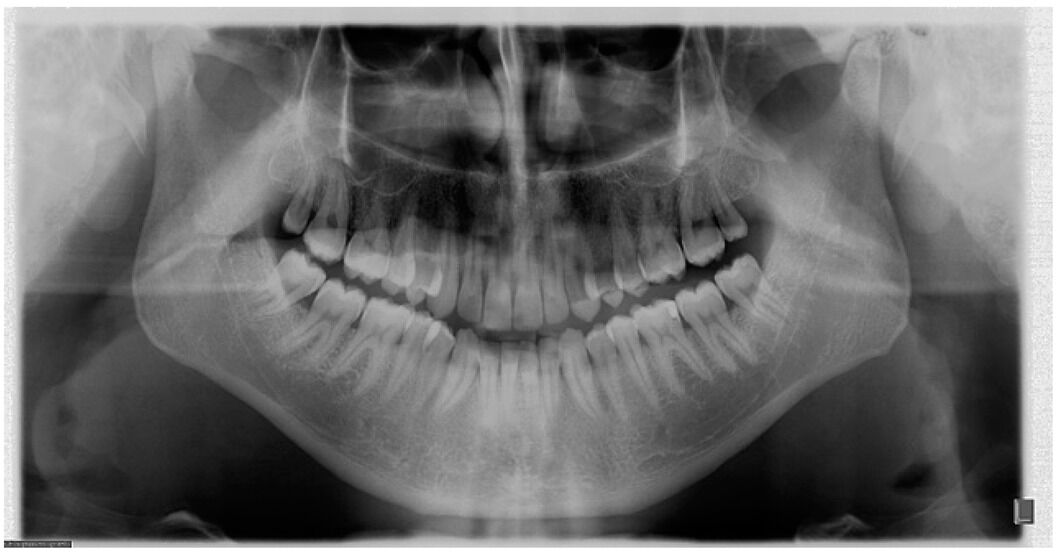

Max Occlusal X Ray . The film/sensor is placed on the occlusal surfaces of the teeth. Occlusal radiographs are made using an extreme bisecting angle technique. • occlusal films are used to show larger areas of the maxilla or mandible. The size of the film is 57 × 76 mm. It defines occlusal radiography and describes the standard projections including upper and lower occlusal, oblique occlusal, and vertex occlusal views. Maxillary occlusal radiographs are taken by using the following procedures: (reduce the kilovoltage 5 kvp if the arch is.